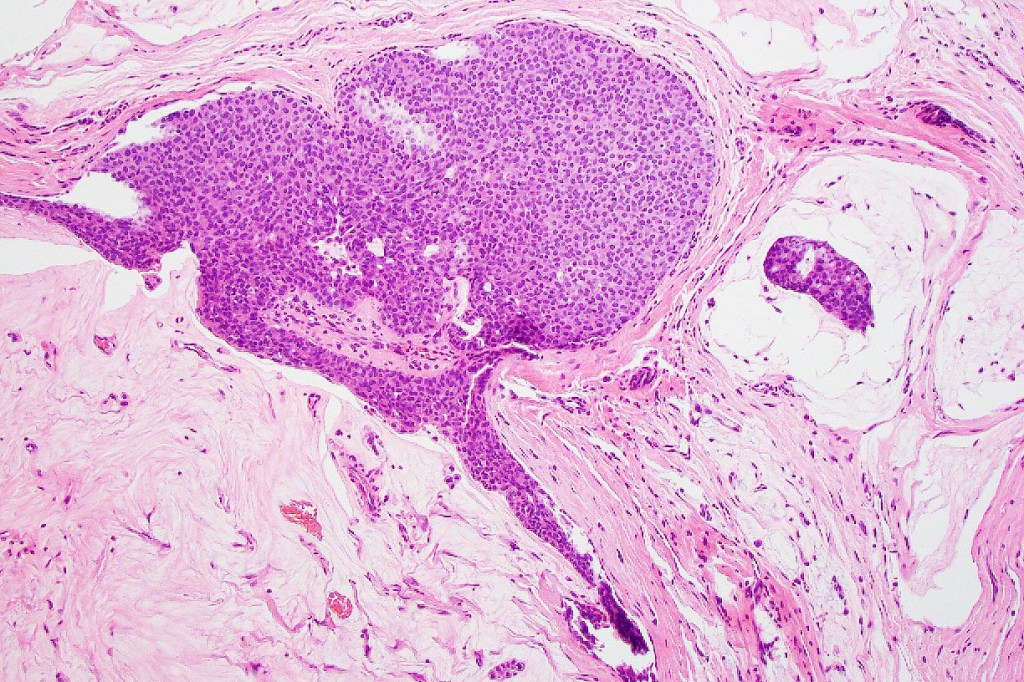

•Mucinous carcinoma is characterized by epithelial islands dispersed in a rich mucinous stroma

•DPAS, colloidal iron & Alcian blue ph 2.5 +ve

•Eosinophilic cytoplasm & small vesicular nuclei

•Mitoses scanty to absent

•No significant pleomorphism

•+/- decapitation secretion

•Exceptionally, signet ring cells

•+/- in situ component